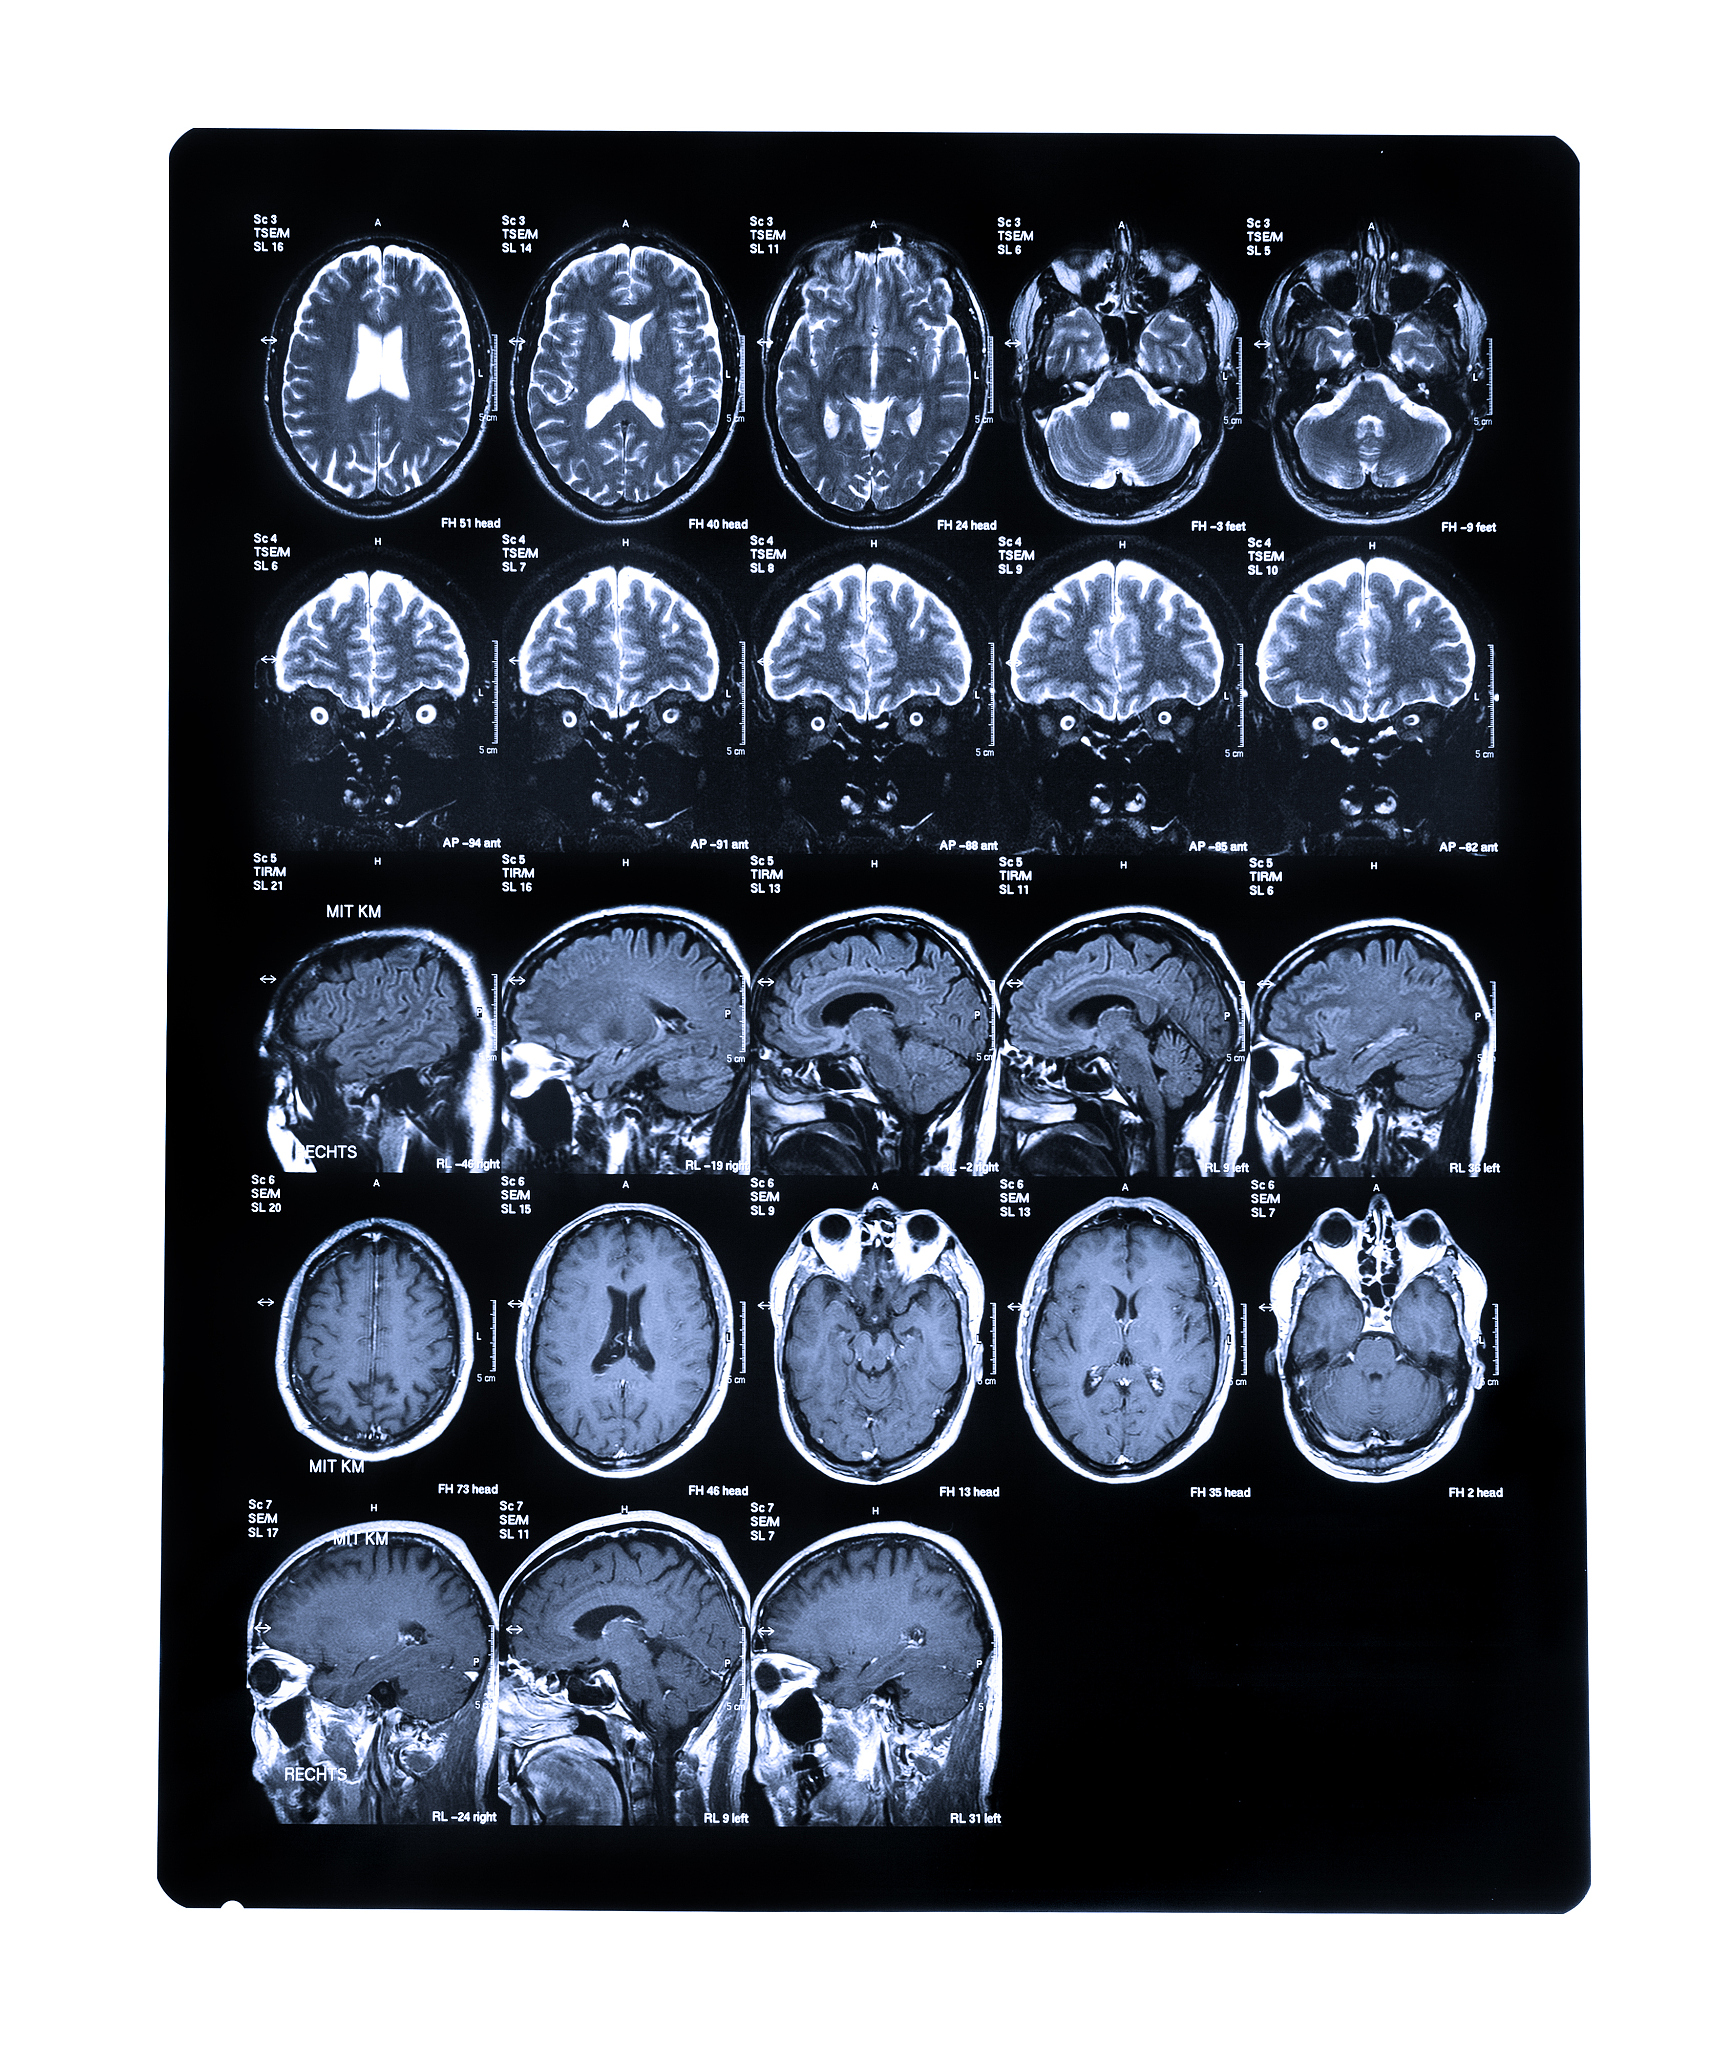

纹状体(striatum)是大脑中的一个重要结构,位于大脑基底节中。它由两个功能区组成:新纹状体(neostriatum)和旧纹状体(paleostriatum)。

新纹状体是纹状体的主要部分,包括两个亚区:尾状核(caudate nucleus)和壳核(putamen)。新纹状体参与运动控制、学习、记忆和奖赏等多种认知和行为功能。

旧纹状体是纹状体中较为原始的部分,也被称为棘核(paleostriatum)。它在进化上较新纹状体更古老,主要参与与本能行为和情感调节相关的功能。

总之,纹状体包括新纹状体和旧纹状体,它们在大脑功能中发挥着不同的作用。